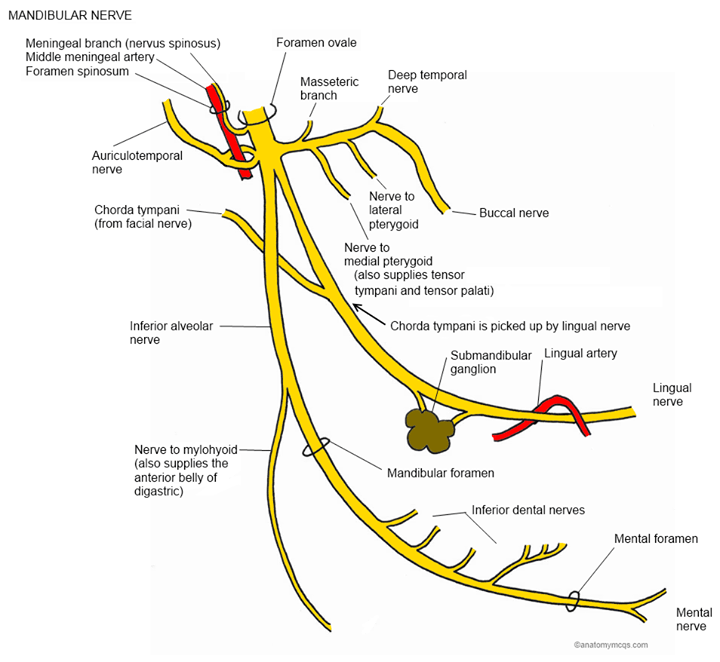

Este nervo sai pelo buraco oval ,depois de se desprender do gânglio do trigémio e origina várias ramas que a seguir se podem ver na imagem.

Irei-me alargar um pouco neste nervo pela sua implicação clinica.

Este nervo, depois da saida, tem de atravessar o músculo pterigoideu lateral pelo que pode ser perturbado a este nivel quando existe uma disfunção da ATM.

O nervo bucal transmite a informação sensitiva da mucosa oral e bochechas. A sensibilidade da porção lateral da cabeça e do couro cabeludo é transmitida pelo nervo auriculo-temporal. Este nervo inerva a zona da ATM, do meato auditivo externo e juntamente com o VII e X também inervam a membrana timpanica (hipersensibilidade do ouvido).

A sensibilidade de todo o maxilar inferior e dois terços anteriores da lingua é transmitida pelo nervo lingual e pelo maxilar inferior. É importante lembrar que o nervo lingual provém da união com o nervo corda do timpano que traz consigo a rama gustativa e parassimpática do VII bis. Por isso sempre que tivermos alterações de sensibilidade ou gosto da lingua devemos avaliar o nervo facial e a rama mandibular do trigémio. Sendo que o trigémio se encarrega do tacto da lingua e temperatura e o facial do gosto.

As fibras sensoriais do queixo e do labio inferior convergem para formar o nervo mentoniano, que entra no buraco mentoniano, local onde pode ser testado se pressionado.

As fibras sensoriais dos nervos alveolares inferiores transmitem a sensibilidade dos dentes inferiores.

A rama motora do nervo mandibular inerva os músculos mastigadores: masseter, temporal, pterigoideu medial e lateral, porcão anterior do digástrico, milohioideu e também o tensor do véu do paladar e tensor do tímpano.

Problemas neste nervo podem dar dor no território cutáneo correspondente, dores nos dentes ou na ATM. Dada a sua relação (apenas sensitiva) com o gânglio sub-mandibular também pode provocar alterações da salivação.

Sempre que suspeitarmos de implicação deste nervo devemos avaliar o esfenoide, o temporal, unidade pterigo-palatina-maxilar e prováveis alterações da ATM , sem esquecer de avaliar cervical superior pois pode estar a facilitar as suturas e as mesmas zonas cutâneas!